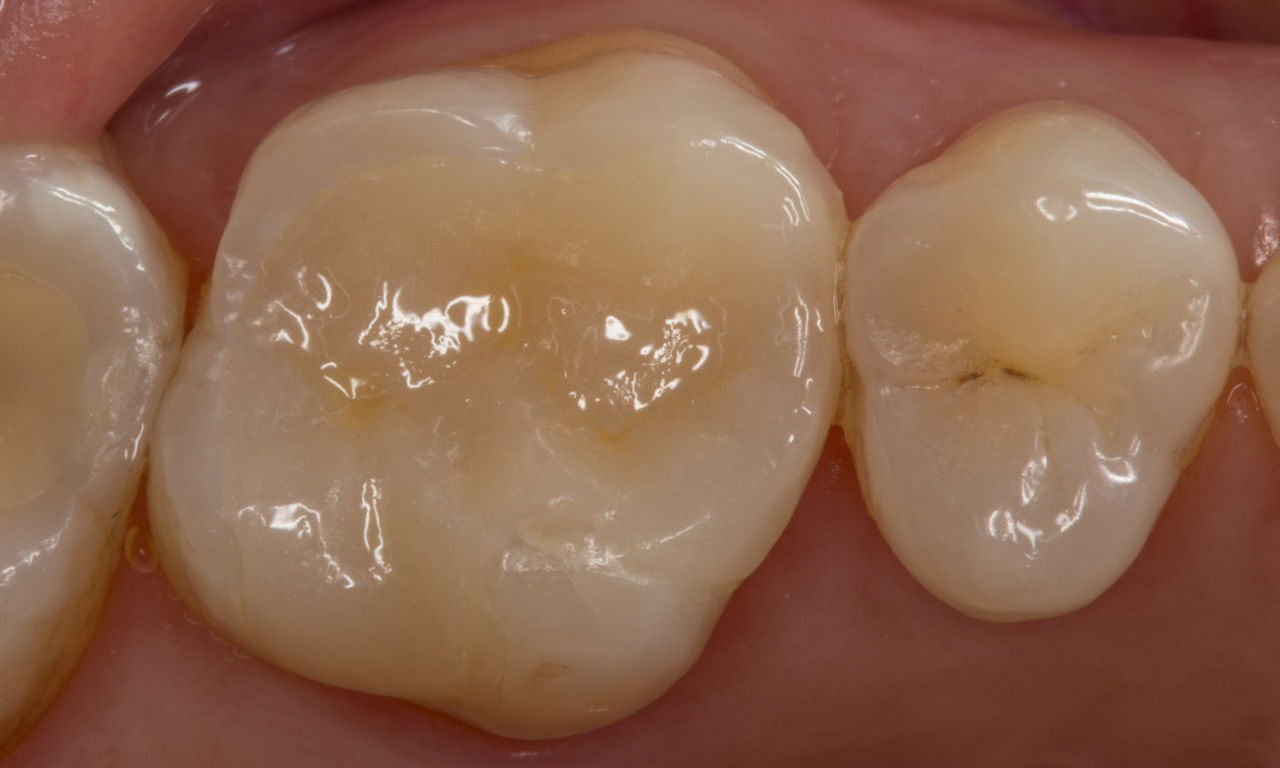

Première molaire supérieure, en 100 minutes

Un inlay CEREC Tessera

La restauration lors d’une consultation unique s’est avérée être une solution particulièrement efficace et confortable pour cette patiente, qui devait effectuer un trajet de 50 kilomètres pour se rendre au cabinet. Un inlay très esthétique a pu être réalisé avec CEREC Tessera.

Avant : Restauration en céramique fracturée réalisée à partir d’une vitrocéramique renforcée à la leucite après une durée d’utilisation clinique de 12 ans.

Après : Restauration fabriquée en consultation à partir d’une céramique avancée au disilicate de lithium CEREC Tessera.